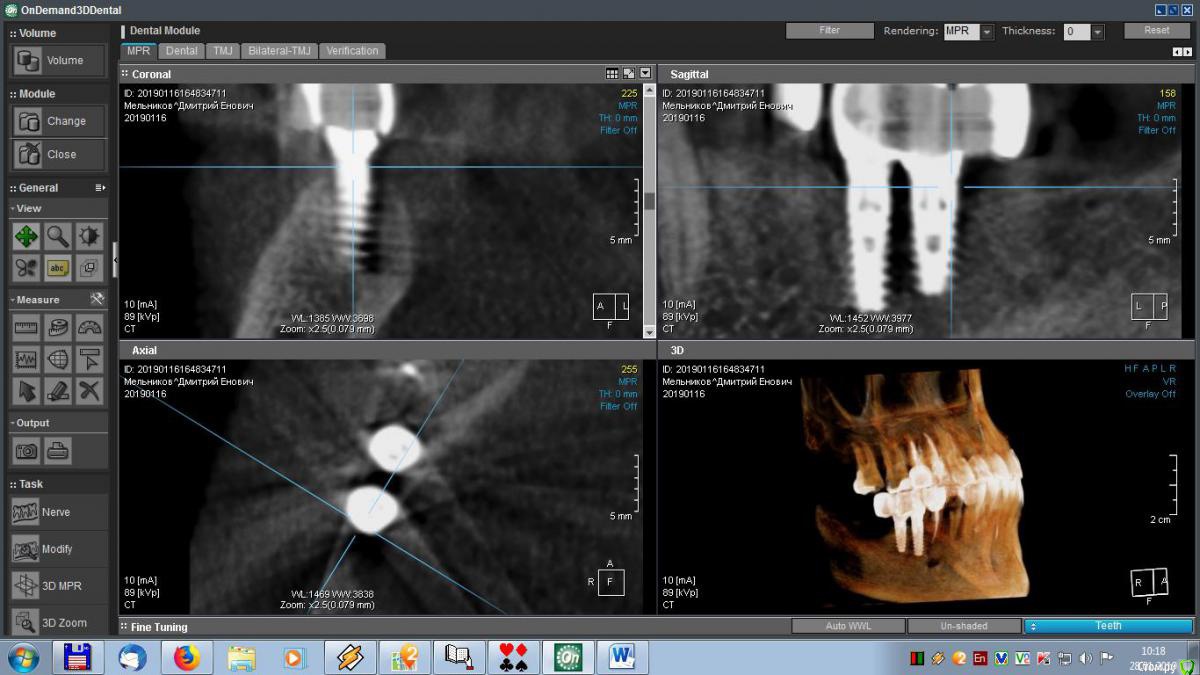

meld Опубликовано 29 января, 2019 Автор Поделиться Опубликовано 29 января, 2019 Здравствуйте, уважаемые доктора! Скоро год, как мне поставили метало-керамические коронки. До сих пор я ощущаю зуд в области имплантатов. На контрольном приеме врач ничего криминального не увидел, прописал чистку, фотосан и КТ, Я все сделал, по КТ врач сказал, что все нормально. Посмотрите, пожалуйста, мои среза и подтвердите (или нет) - все ли нормально. Спасибо. Ссылка на комментарий

meld Опубликовано 29 января, 2019 Автор Поделиться Опубликовано 29 января, 2019 Выложил больше срезов. Спасибо. Ссылка на комментарий

Борис80 Опубликовано 29 января, 2019 Поделиться Опубликовано 29 января, 2019 Все нормально, если не скапливается постоянно пища под дальним краем 7го зуба Ссылка на комментарий

Bier Опубликовано 30 января, 2019 Поделиться Опубликовано 30 января, 2019 на мой взгляд тоже все ок. Ссылка на комментарий